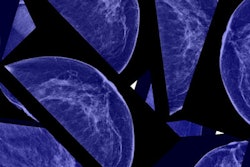

The National Health Service (NHS) Scotland is contacting nearly 1,800 women following revelations that they did not receive invitations to their final round of breast screening.

Scottish women between the ages of 50 and 70 are routinely contacted for screening, but delays in the program meant 1,761 women were not invited for their final screen by the time they turned 71, according to a report from the BBC.